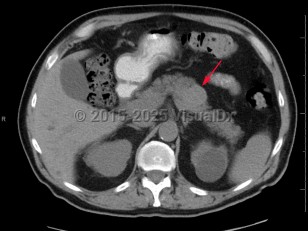

Imaging Studies image of Pancreatic carcinoma - imageId=6846876. Click to open in gallery.  caption: 'Axial non-contrast CT image demonstrates a relatively hyperattenuating mass within the body of the pancreas. Pathology was consistent with pancreatic neuroendocrine tumor.'

Axial non-contrast CT image demonstrates a relatively hyperattenuating mass within the body of the pancreas. Pathology was consistent with pancreatic neuroendocrine tumor.